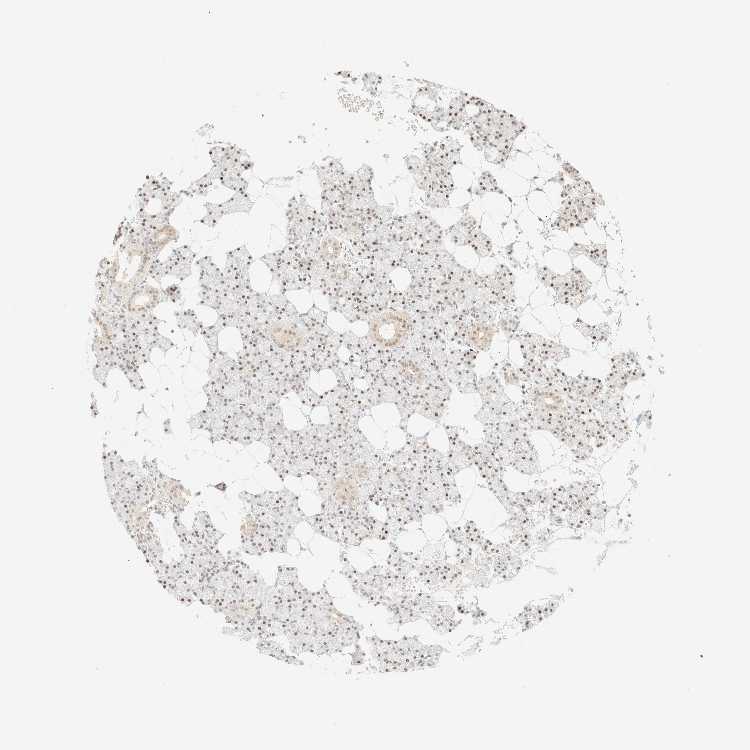

SALIVARY GLAND - Antibody stainingi

Antibody staining in the annotated cell types in the current human tissue is reported as not detected, low, medium, or high, based on conventional immunohistochemistry profiling in selected tissues. This score is based on the combination of the staining intensity and fraction of stained cells.

Each image is clickable and will lead to virtual microscopy that enables deeper exploration of all samples and also displays staining intensity scores, fraction scores and subcellular localization as well as patient and tissue information for each sample.

Antibody HPA024434

Glandular cells Medium